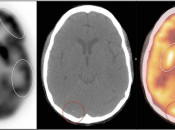

Brain

As the brain fully relies on glucose metabolism, it demonstrates rather diffuse intense uptake of FDG. In fact, its metabolic activity is so intense, that most PET reading software programs will require the reader to manually decrease its intensity to evaluate the brain for potential lesions.

Familiarity with the normal symmetric uptake of FDG in the brain will help the reader identify primary brain tumors and metastatic lesions.

Areas of normal relative increased uptake include the grey matter, basal ganglia, frontal eye fields, posterior cingulate gyrus and visual cortex. Symmetry of uptake should be preserved.